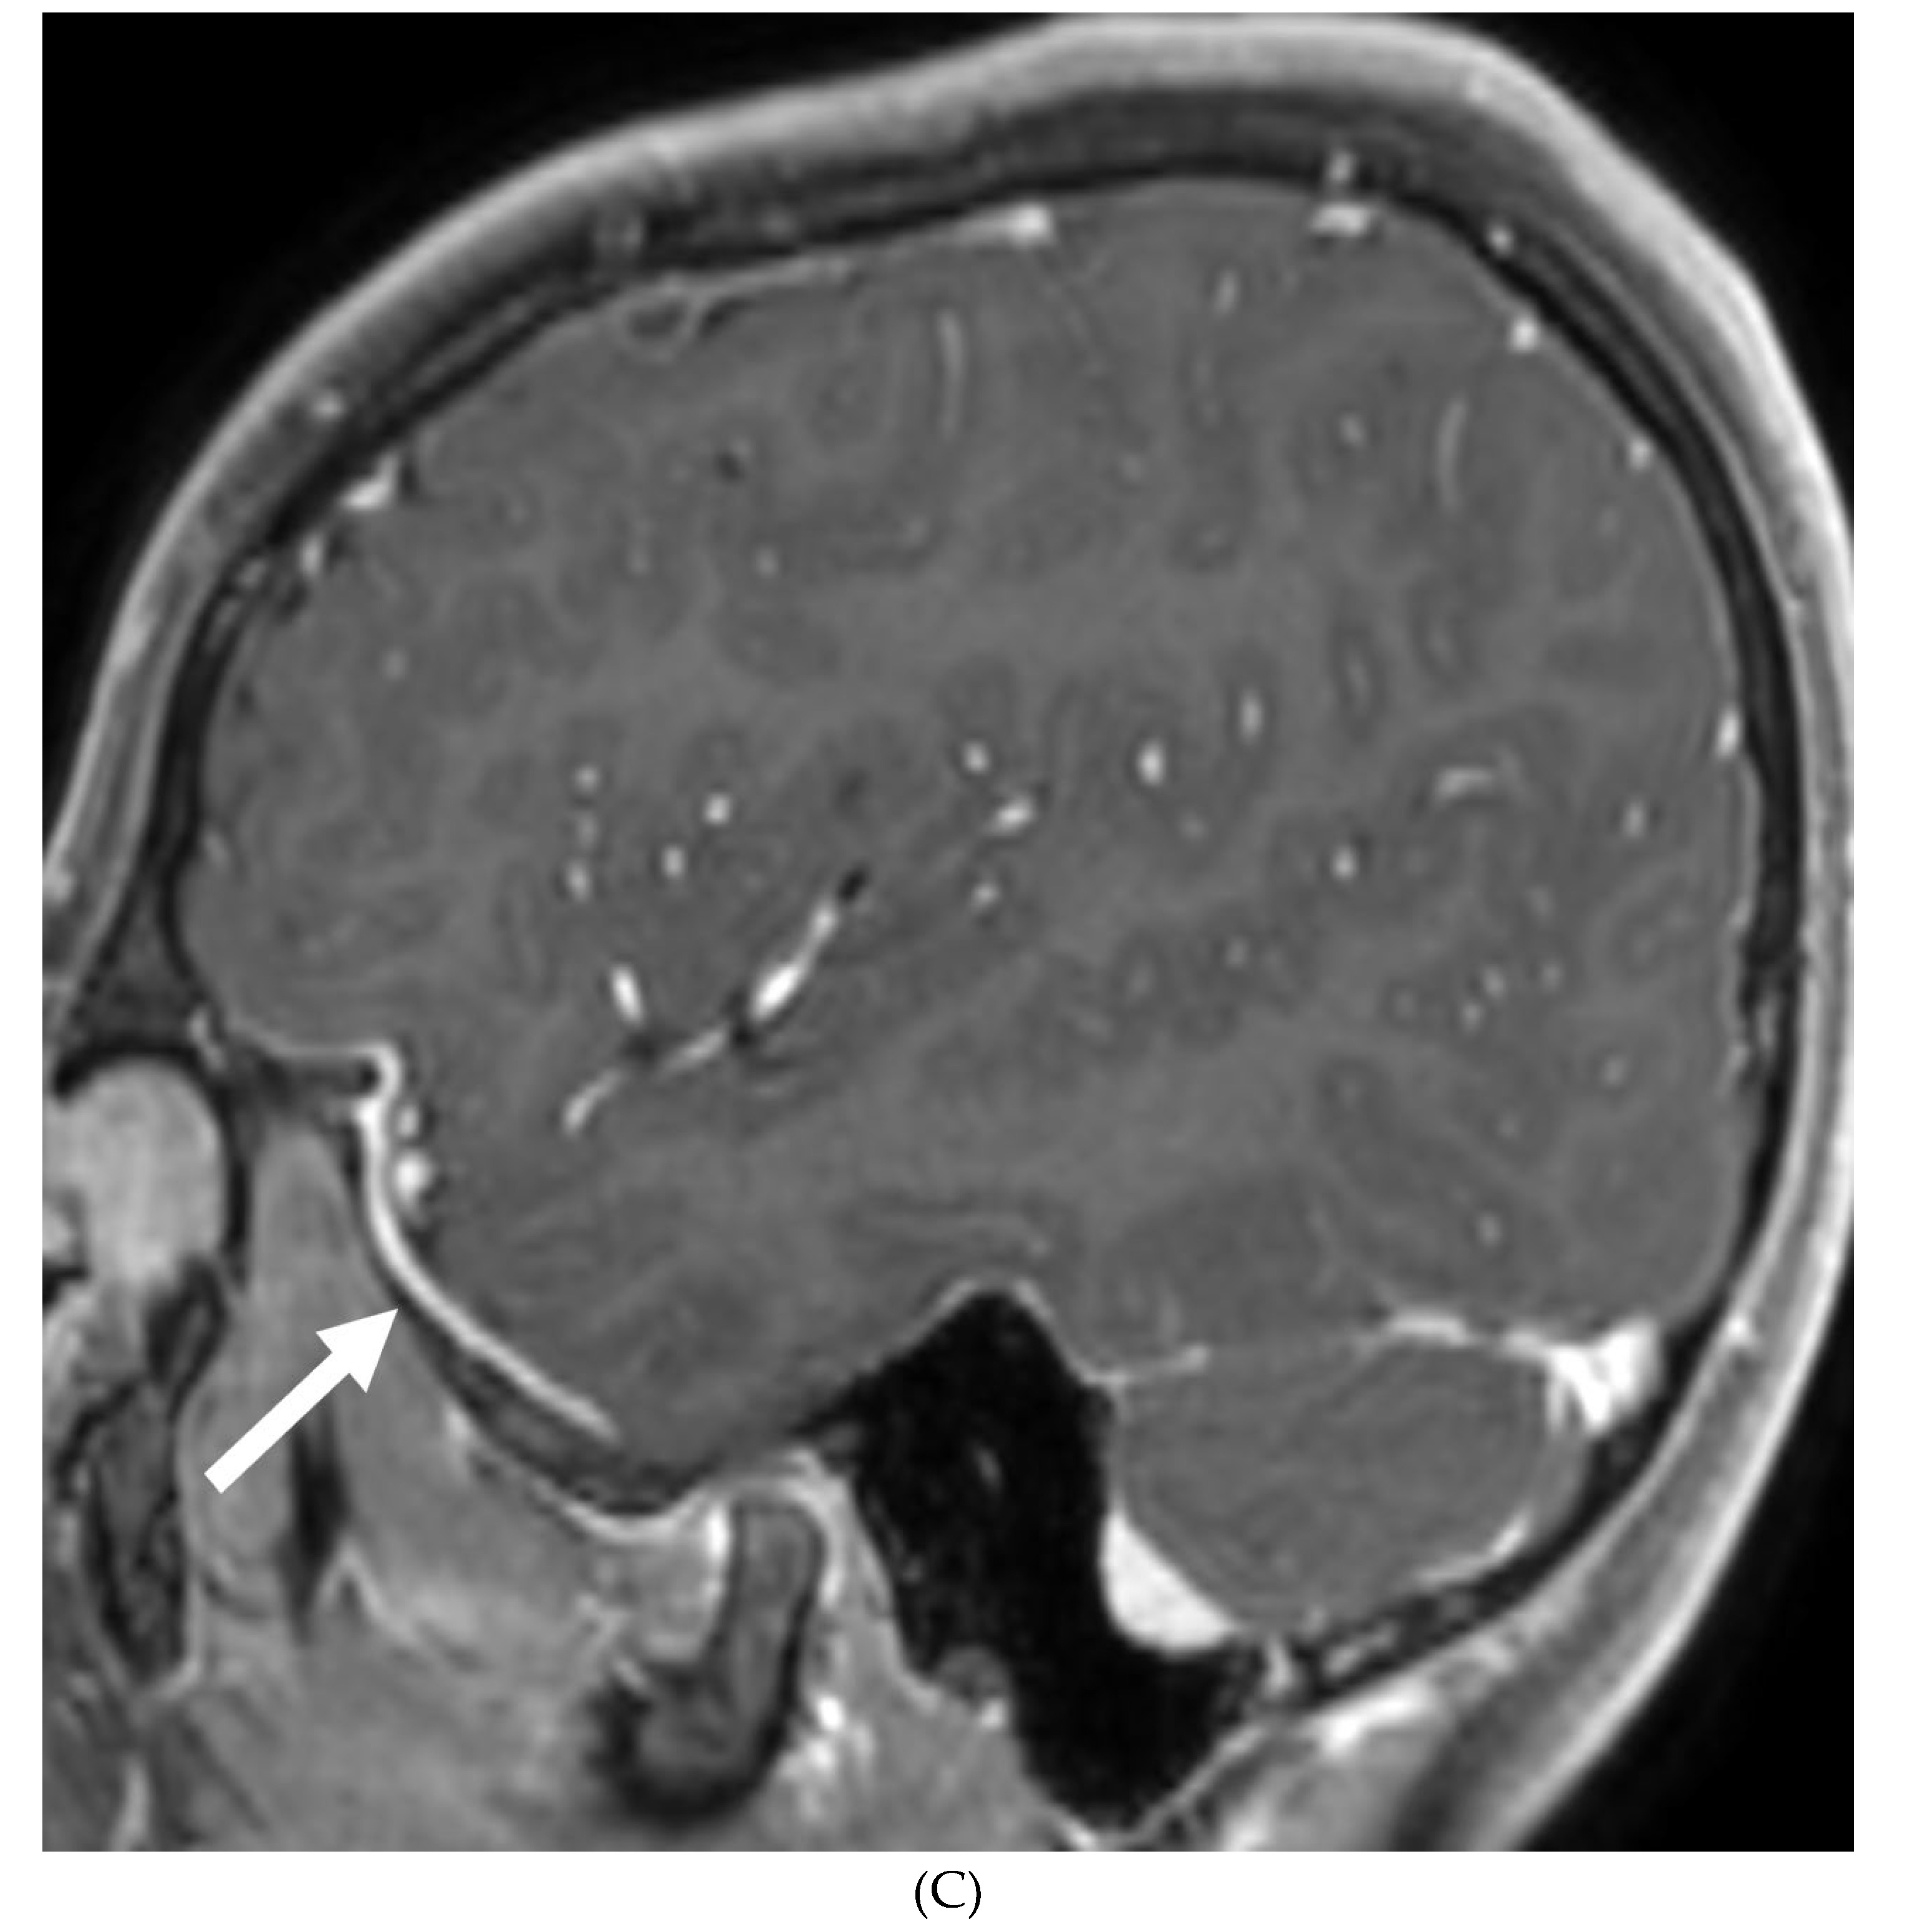

MENINGIOMA